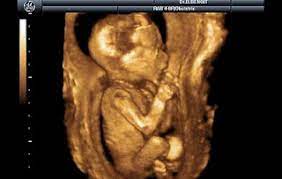

Hep merak edilmiştir. Merak edilmesi de oldukça doğaldır. Çünkü annenin canından can olan en değerlisi olan bebeğinin görüntüleridir. Bebek 18. Hafta da ultrason da belirgin olmaya başlar. Bu olay artık bebekle tanışmaktır. Yaklaşık 4 ay karnınızda büyüyen bebeğin az da olsa şekillenmiş halini görürsünüz. Çünkü bu evrede artık çocuğun kılları, tırnakları, kafası, kolları ve bacakları tam olarak olmasa da belirginleşmeye başlar. 18. Hafta itibariyle ultrasona düzenli olarak girilmelidir ki çocuğun gelişimi ve aksaklıklarını görebilmek daha rahat olur. Tabi ki bu evrede çocuk ve anne oldukça hassastır. Bebeğin organları ve vücudu tam olarak şekillenmediği için anne adayının her konuda çok dikkatli ve düşünceli olması gerekmektedir. Çünkü yapacağı her olumlu veya olumsuz hareket direk olarak bebeği etkilemektedir. Bu evrede dolaşım sisteminde oluşan aksaklıklardan dolayı kadınlarda tansiyon düşmesi gibi durumlar doğaldır. Bu durumlar da heyecandan uzak durup dikkatli ve temkinli hareket etmek gerekir. Çünkü heyecanlı ve kendini bilmez tavırlar hem bizi hem de bebeğimizi zor duruma sokabilir. Tansiyon düşme durumu ani yapılan hareketlerde de sıklıkla görülebilir. Buna örnek olarak oturulan yerden aniden hızlı bir şekilde kalkmak diyebiliriz. Bu durumla karşılaştığımız zaman klasik yöntemleri kullanmak yerine ayaklarımızı vücudumuzdan yüksek bir yere koyup bir müddet uzanmamız gerekmektedir. Bu sayede çok kısa bir zaman aralığında tansiyonumuz normal haline gelip baş dönmemiz geçer. Tüm gebelik döneminde sorulduğu gibi bu dönemde de anne ve baba adayları çocuğunun sağlıklı olup olmayacağını hep sorar kendi kendine. Bu dönemde baskın olmakla beraber bebeklerin zihinsel gelişimleri de gelişmeye başlar. Bu bağlamda anne ve baba adaylarına oldukça büyük görevler düşmektedir. Anne karnındayken bebekle konuşmak yani iletişime geçmek oldukça önemlidir. Bebek anne karnında size duyabildiği ve yaptığınız hareketleri algılayabildiği için bu durumda olumlu veya olumsuz bir şeklide kesinlikle etkilenir. Bu tarz olumsuz olaylardan uzak kalabilmek için özellikle gebelik zamanında yaptığımız davranışlara çok dikkat etmemiz gerekmektedir. Eğer dikkat etmez isek çocuğumuzda zihinsel ve fiziksel aksaklıklar olabilir. Bunları engellemek bizim elimizde.